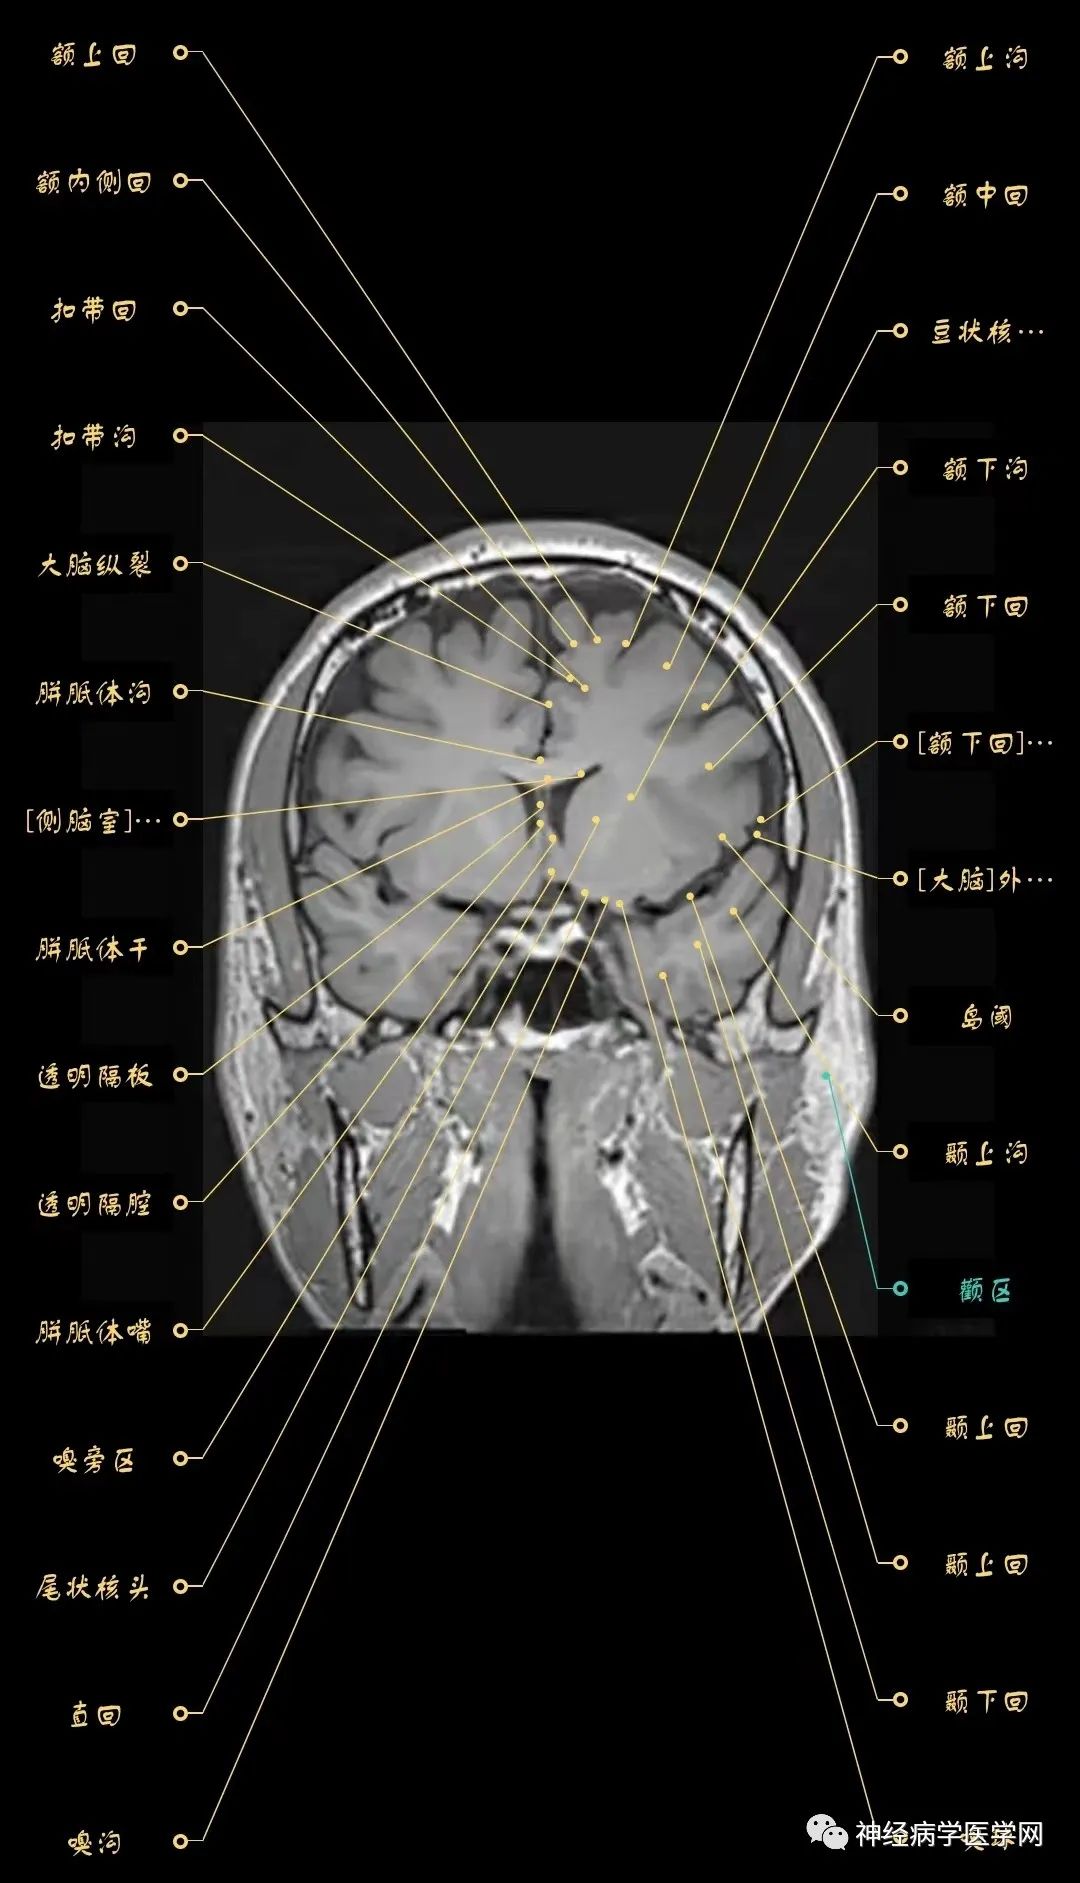

大脑mri影像(冠状面)

神经影像解剖系列颅脑mri超详细三维标注震撼来袭

大脑磁共振成像,冠状面